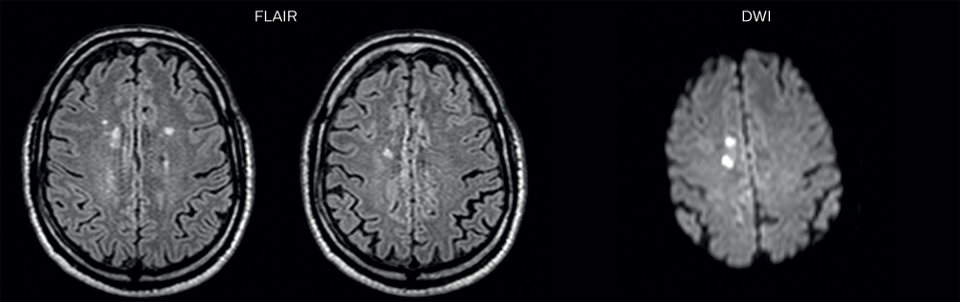

On FLAIR images we can see some nonspecific high signal abnormalities in frontal white matter bilaterally. On DWI we can see acute ischemic lesions which appear with high signal intensity. Arrows show vessel wall enhancement which appears concentric and homogeneous in different cerebral territories.

On the routine MR sequences that we did, we could see acute ischemic lesions. We see them very well on the diffusion images, where acute ischemic lesions usually appear with high signal intensity and restricted diffusion. However, the etiology of these lesions cannot be derived from these images. An area of restricted diffusion was seen in the anterior cerebral artery territory and we concluded it was an ischemic lesion. On MR angiography we can just see if there is stenosis or vessel occlusion, but it does not provide us information on the etiology of this kind of lesion. So, we decided to perform Black Blood imaging. The presence and the pattern of vessel wall enhancement on Black Blood imaging, can help us to determine the etiology of the lesion. differentiate vasculitis from other causes of vasculopathy, such as atherosclerosis, with a high specificity [1-3]. In an atherosclerotic lesion, vessel wall thickening and enhancement are usually eccentric, while in vasculitis the wall thickening and enhancement are usually concentric, homogenous, and in a long portion of the vessel. of patients whenever their treatment is installed in order to determine the efficacy of a particular treatment. In this case the Black Blood imaging helped us to suggest the diagnosis of HIV-related brain vasculitis.